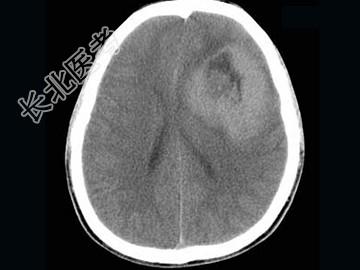

- 单项选择题男,15岁, 进行性头痛1年余,CT检查, 最可能的诊断为 ( )

A、脑膜瘤

B、脑血管畸形

C、转移瘤

D、淋巴瘤

E、胶质母细胞瘤